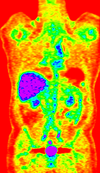

lleft whole body CT baseline lleft whole body PET baseline lleft whole body CT follow-up lleft whole body PET follow-up

CT: 512 x 512 x 267

0.97 x 0.97 x 3.27 mm

PET: 128 x 128 x 267

4.7 x 4.7 x 3.3 mm

CT: 512 x 512 x 195

0.98 x 0.98 x 5.0 mm

PET: 168 x 168 x 195

4.1 x 4.1 x 5 mm